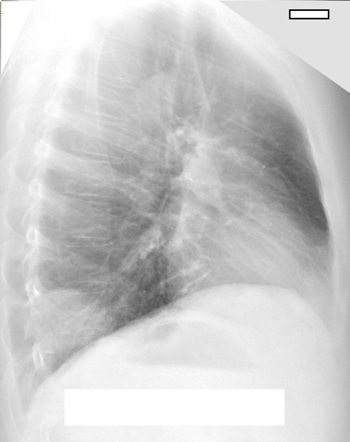

Доктором-рентгенологом, КТ-диагностом Кушман М.А. пациенту была выполнена рентгенография органов грудной клетки в прямой и боковой проекциях.

На рентгенограммах был обнаружен участок неоднородного понижения прозрачности лёгочной ткани правого лёгкого. Данные изменения были трактованы, как правосторонняя нижнедолевая сегментарная пневмония.